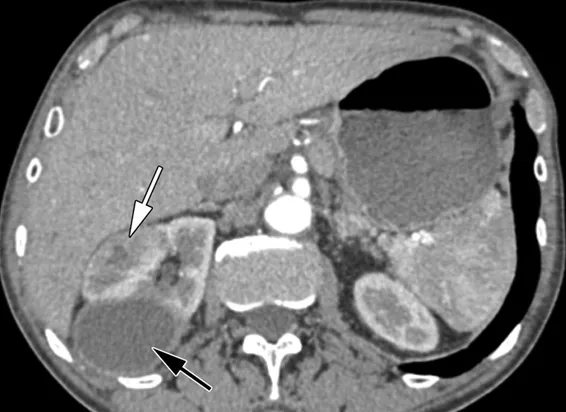

DRPAD além do Tolvaptana: Novas Perspectivas Terapêuticas nas Diretrizes KDIGO 2025

Além do tolvaptana, as diretrizes KDIGO destacam a importância de medidas não farmacológicas e abordagens complementares no manejo da DRPAD, como controle rigoroso da pressão arterial, redução de ingesta de sal e aumento de ingestão hídrica. Estudos em andamento também avaliam terapias-alvo envolvendo vias do mTOR, cAMP e inflamação. O manejo multidisciplinar permanece essencial para retardar a progressão da doença e melhorar a qualidade de vida.

Uso do Tolvaptan na DRPAD: O Que falam nas Novas Diretrizes KDIGO 2025?

As novas diretrizes KDIGO para a Doença Renal Policística Autossômica Dominante (DRPAD) atualizam os critérios de elegibilidade para o uso de tolvaptana, com ênfase na estratificação do risco de progressão rápida. O documento reforça a individualização da terapia com base em subclassificação por imagem (Mayo Clinic) e função renal. A incorporação prática dessas recomendações pode otimizar o manejo e retardar a progressão da DRC nesses pacientes.